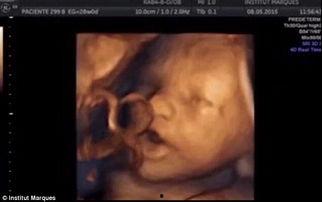

当宝宝来到这个世界的时候,他们通常只有18周大。这时候的宝宝,已经从一个小小的胚胎,变成了一个有模有样的胎儿。通过一段18周胎儿视频,我们可以看到,宝宝的小脸蛋已经初具轮廓,眼睛虽然还是闭着的,但已经可以看到眼皮和眼珠的形状。宝宝的耳朵、鼻子、嘴巴都已经成形,甚至手指和脚趾也清晰可见。

在这个阶段,宝宝的皮肤是半透明的,你可以看到血管在皮肤下流动。宝宝的头发也开始生长,虽然还很细软,但已经可以辨认出头发的颜色。而且,宝宝的小手和小脚已经开始活动,虽然我们看不到具体的动作,但可以想象,这个小生命正在妈妈肚子里自由地伸展、踢腿。